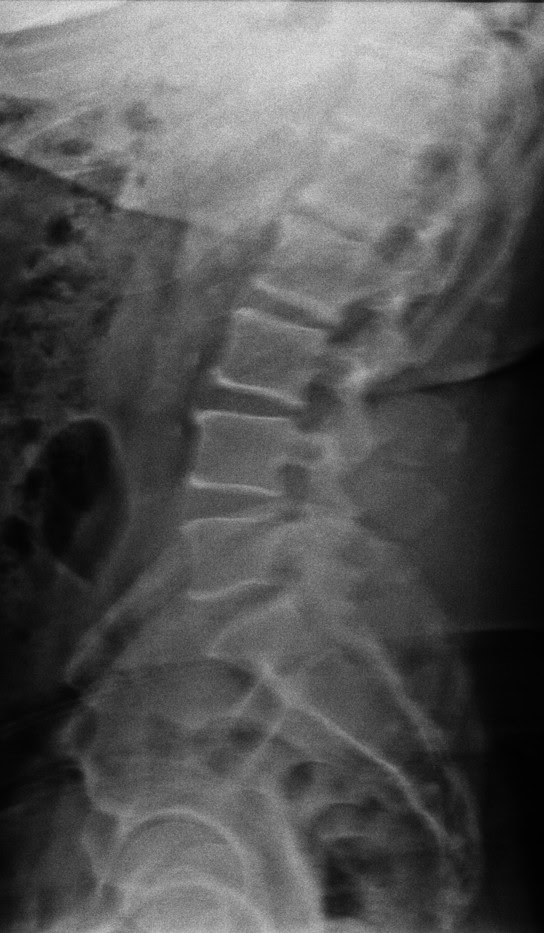

Today, Ed has seen progress in multiple areas of his health. His sleep has improved, allowing him to feel more rested and energized each day, and he is walking more comfortably and confidently than he has in months. Ed continues to visit us for his weekly adjustments, maintaining the progress he has worked so hard to achieve and continuing to build strength, mobility, and balance.

We are truly honored to be part of Ed’s healing journey and are grateful for the trust he has placed in us. Watching his determination and progress over the years has been incredibly inspiring, and we are proud to support him every step of the way as he continues toward better health and greater independence.